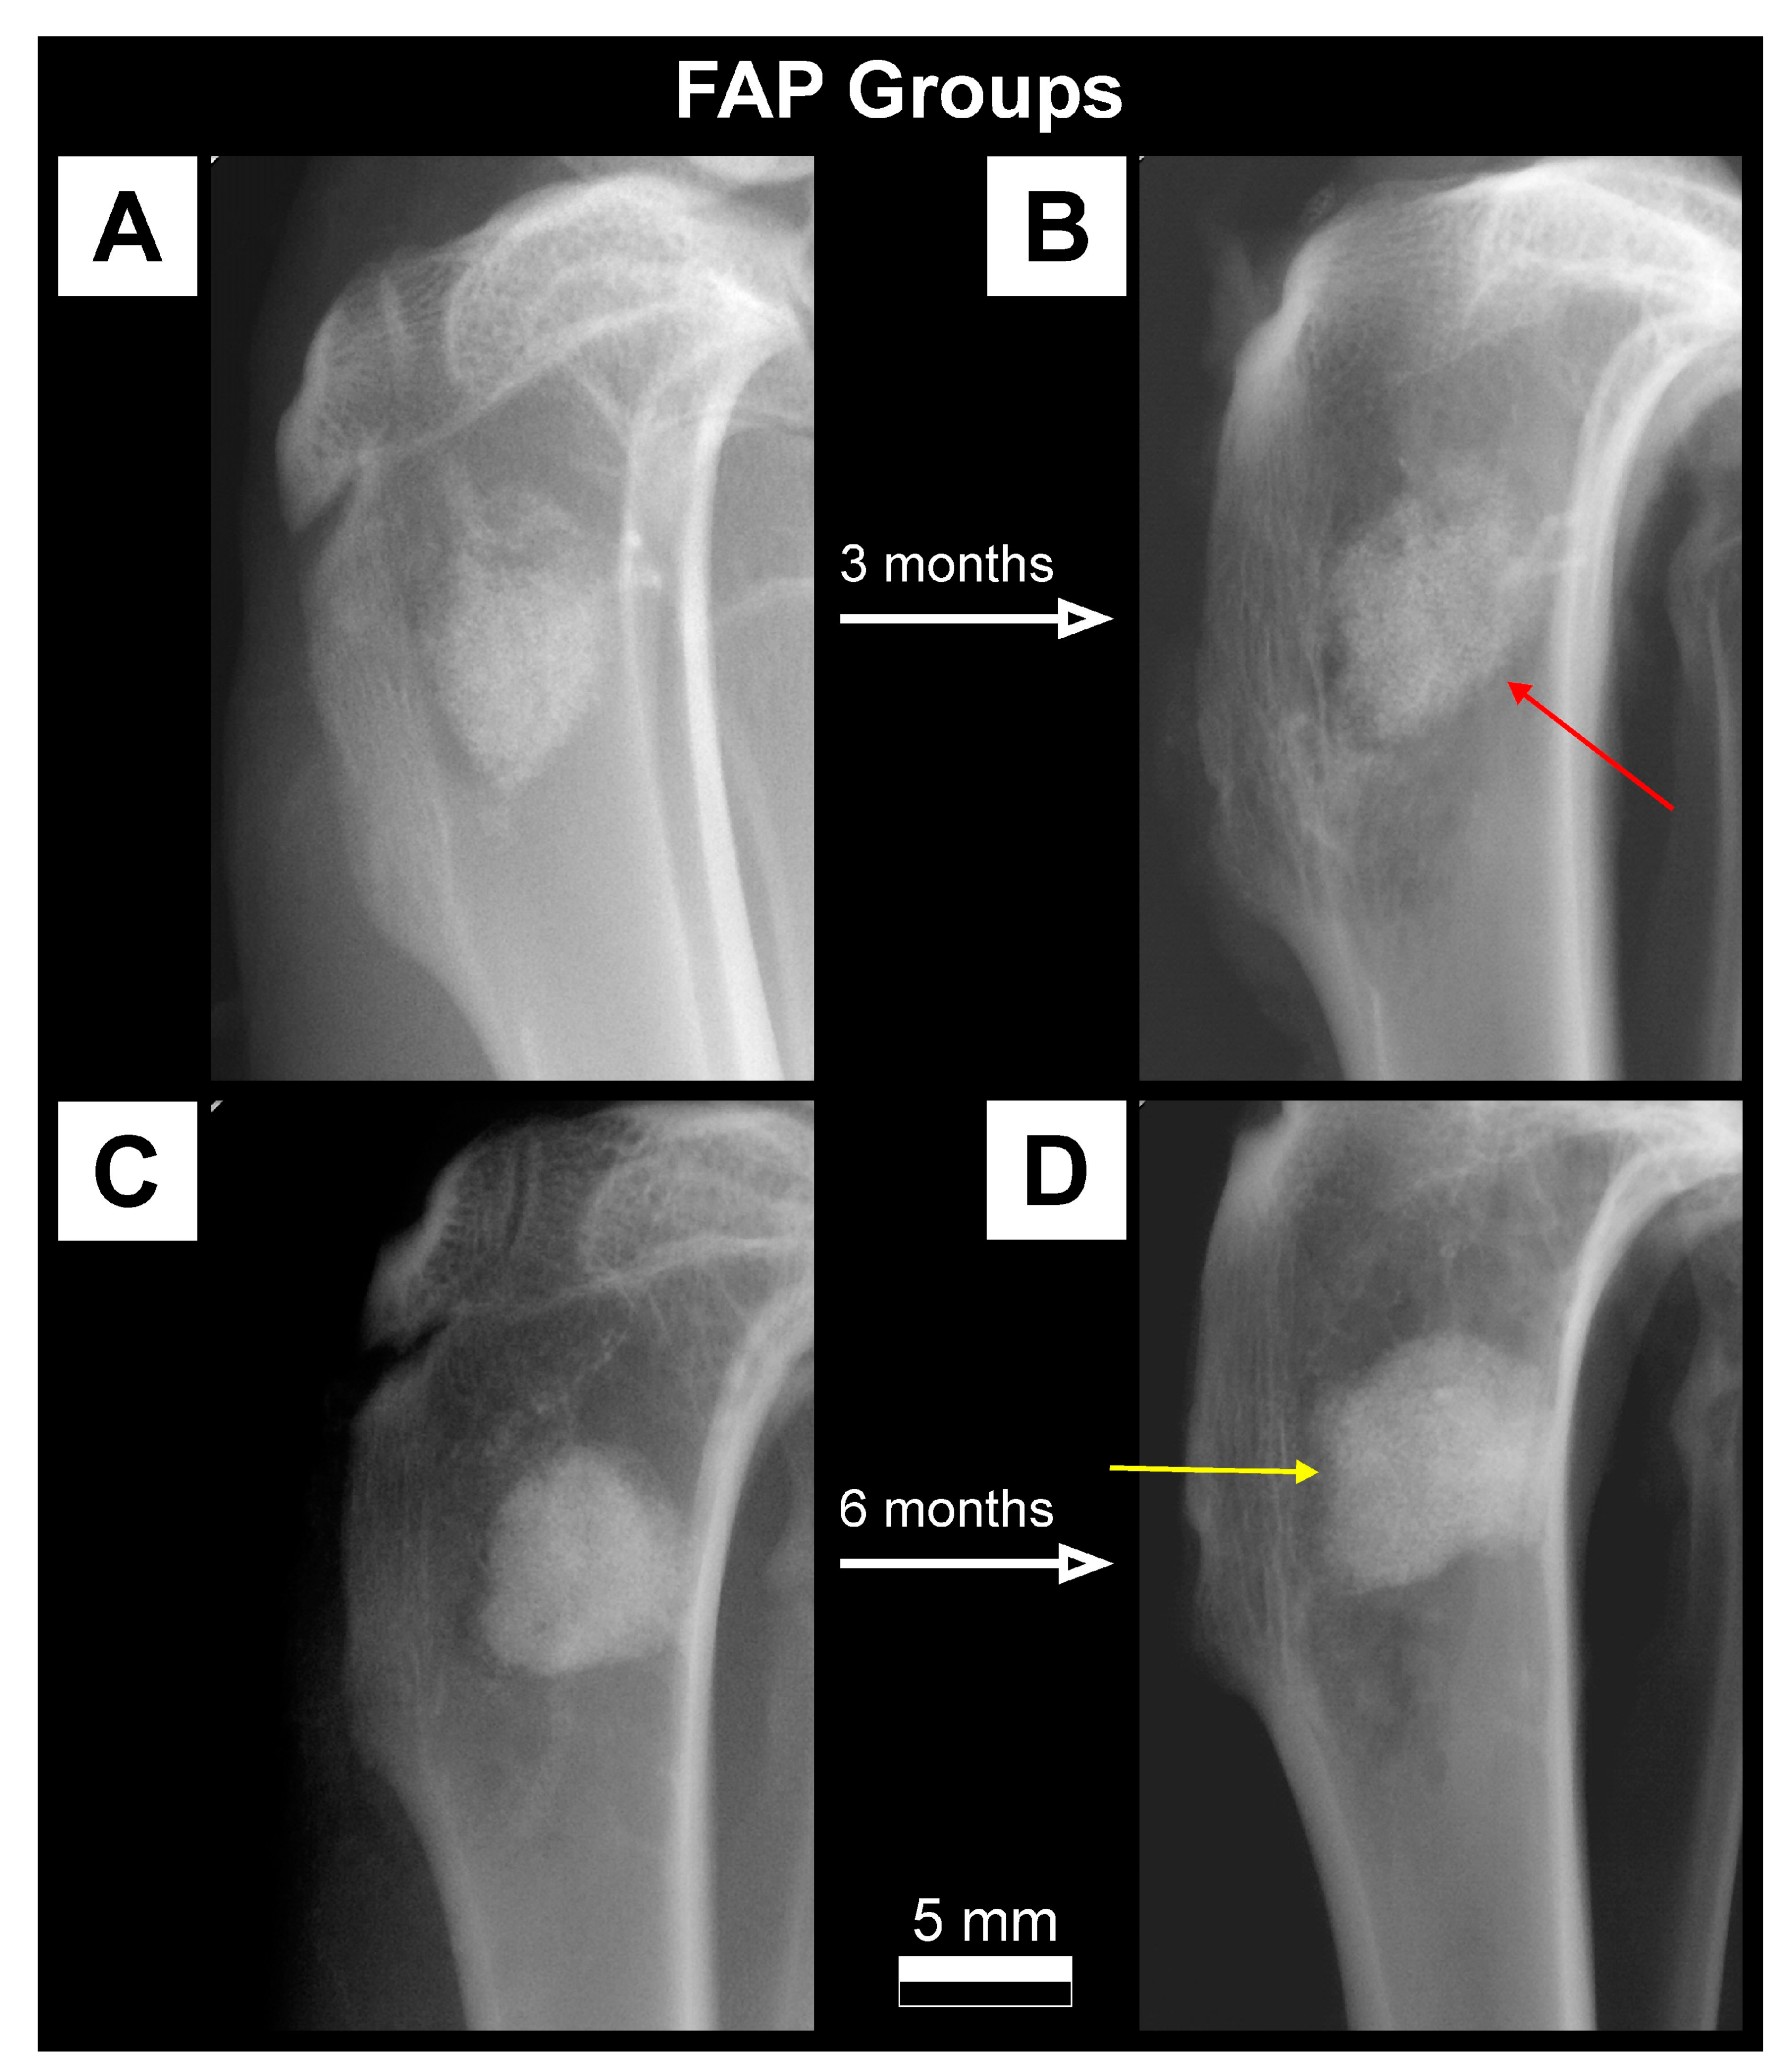

- FAP: Rabbits that have implanted FAP granules (n = 18);

2.3.1. X-ray Imaging—Conventional Radiography

3.1. Qualitative Analysis of Bone Substitute Materials